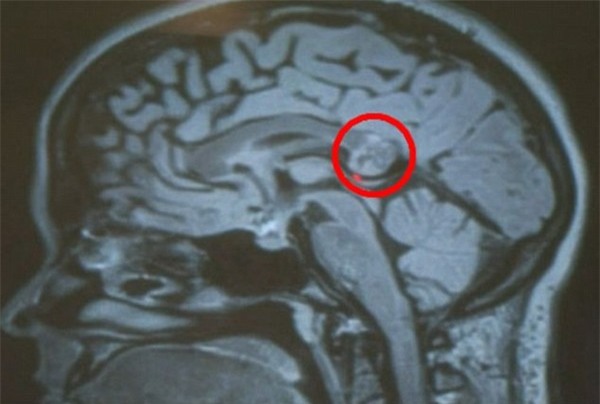

Trường hợp song sinh sống ký sinh của Yamini Karanam, cô gái trẻ 26 tuổi, người Mỹ đã gây sốc cho các bác sĩ tại bệnh viện nơi cô điều trị khi họ phát hiện ra trong não bộ của cô có một khối u hình thành đầy đủ xương, tóc và răng như con người. Được biết, khối u kỳ quái này chính là bào thai của người chị em song sinh sống ký sinh của Yamini.

Ban đầu, các bác sĩ cũng không thể xác định rõ được bệnh tình của cô sinh viên này cho tới khi tiến hành phẫu thuật qua một lỗ nhỏ trên hộp sọ. Lúc này, họ mới phát hiện ra khối u nằm bên trong não bộ chính là bào thai người chị em song sinh không thể phát triển hoàn thiện và đã chết cua Yamini.

Với cấu trúc xương, răng và tóc đã hình thành đầy đủ, khối u này trong thuật ngữ y học được gọi là u quái. Bác sĩ Hrayr Shahinian, Học viện nghiên cứu Hộp sọ tại Los Angeles cho biết, trong số 8.000 ca u não mà ông từng tiếp nhận, đây mới là ca u quái thứ hai mà ông gặp phải.